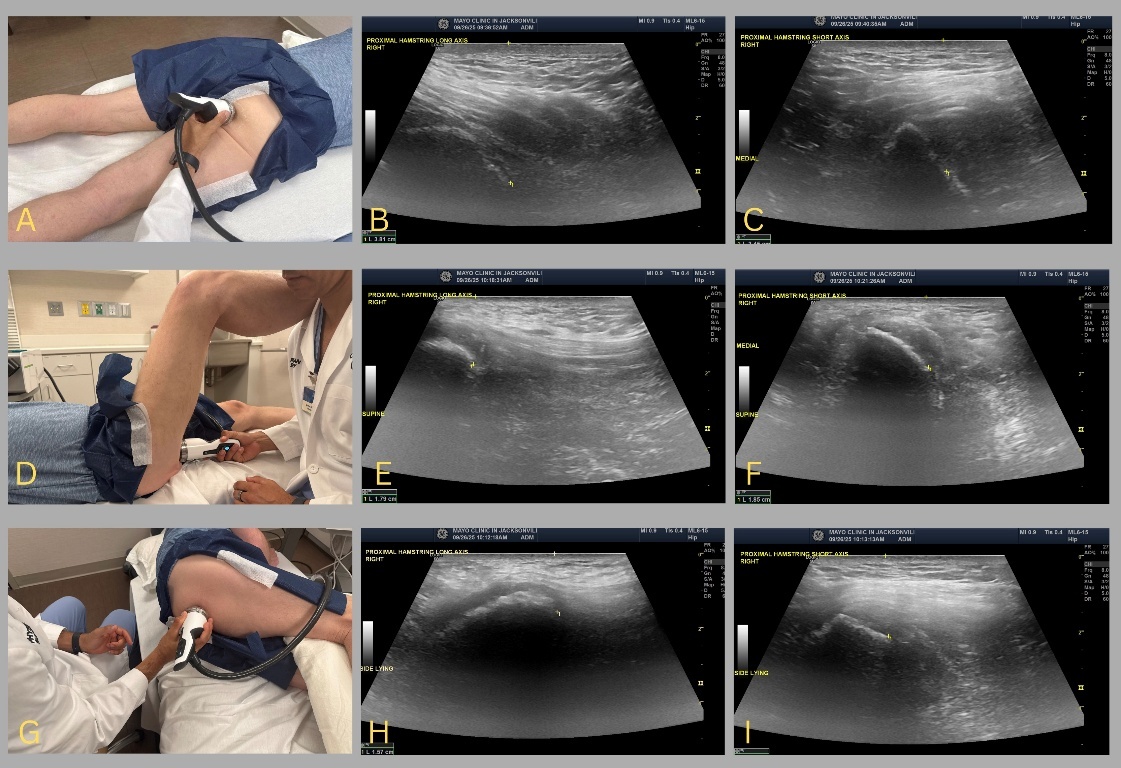

While clinical focusing has been described as a technique for both RPW and FSW, delivering treatment over the area of maximal pain reported by the patient, the position of a patient may alter how the sounds waves are transmitted and dissipated when targeting the proximal hamstring tendon. When in the prone position, the proximal hamstring is less exposed than in other positions, and, depending on the patient’s body habitus, adipose and subcutaneous tissue may act as a barrier to directly targeting the origin of the hamstring. Understanding the depth needed to adequately target the structure of interest is important as each device has a set focal zone of maximal energy which can be altered with different standoffs and/or the device used (e.g. RPW or FSW). A brief diagnostic musculoskeletal ultrasound to determine depth of the hamstring in the various different positions and can aid in localizing the proximal hamstring in relation to the skin surface (Figure 2). Additionally, if a shorter tip standoff is utilized to achieve a deeper focal zone, an inadvertent consequence may be that sound waves propagate to the anterior hip or adjacent neurovascular structures (e.g. pudendal nerve). The prone approach may be comfortable for most patients and is ergonomically efficient for the clinician administering the treatment. This approach may be more familiar to clinicians, as this position is commonly utilized for injection techniques.

While the supine with hip and knee flexed approach exposes the origin of the hamstring, this position may be hard to sustain for a patient and is less ergonomically efficient for the clinician (Figure 2D). However, since this position induces compression of the proximal hamstring against the ischial tuberosity, it may simulate a typical position that patients experience pain, increasing the utility of clinical focusing.

Based on the reported literature and sonographic depth depicted in Figure 2, when treating PHT with RPW or FSW, the author’s preferred approach involves having the patient side lying with the hip and knee flexed (Figure 2G). The degree of hip and knee flexion can vary based on patient comfort and body habitus, however there should be enough flexion to expose the proximal hamstring. A pillow is often utilized between the legs to improve patient comfort. While in this position, the patient and clinician’s comfort are maximized, and it does not require the patient to hold a sustained position. Additionally, the degree of hip and knee flexion can be easily adjusted as needed. This position also achieves the compression of the proximal hamstrings on the ischial tuberosity.